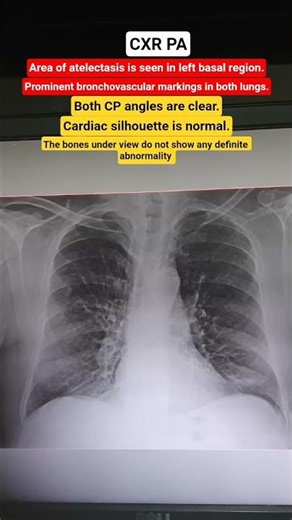

On CXR - What Is Atelectasis

On X-ray - Atelectasis